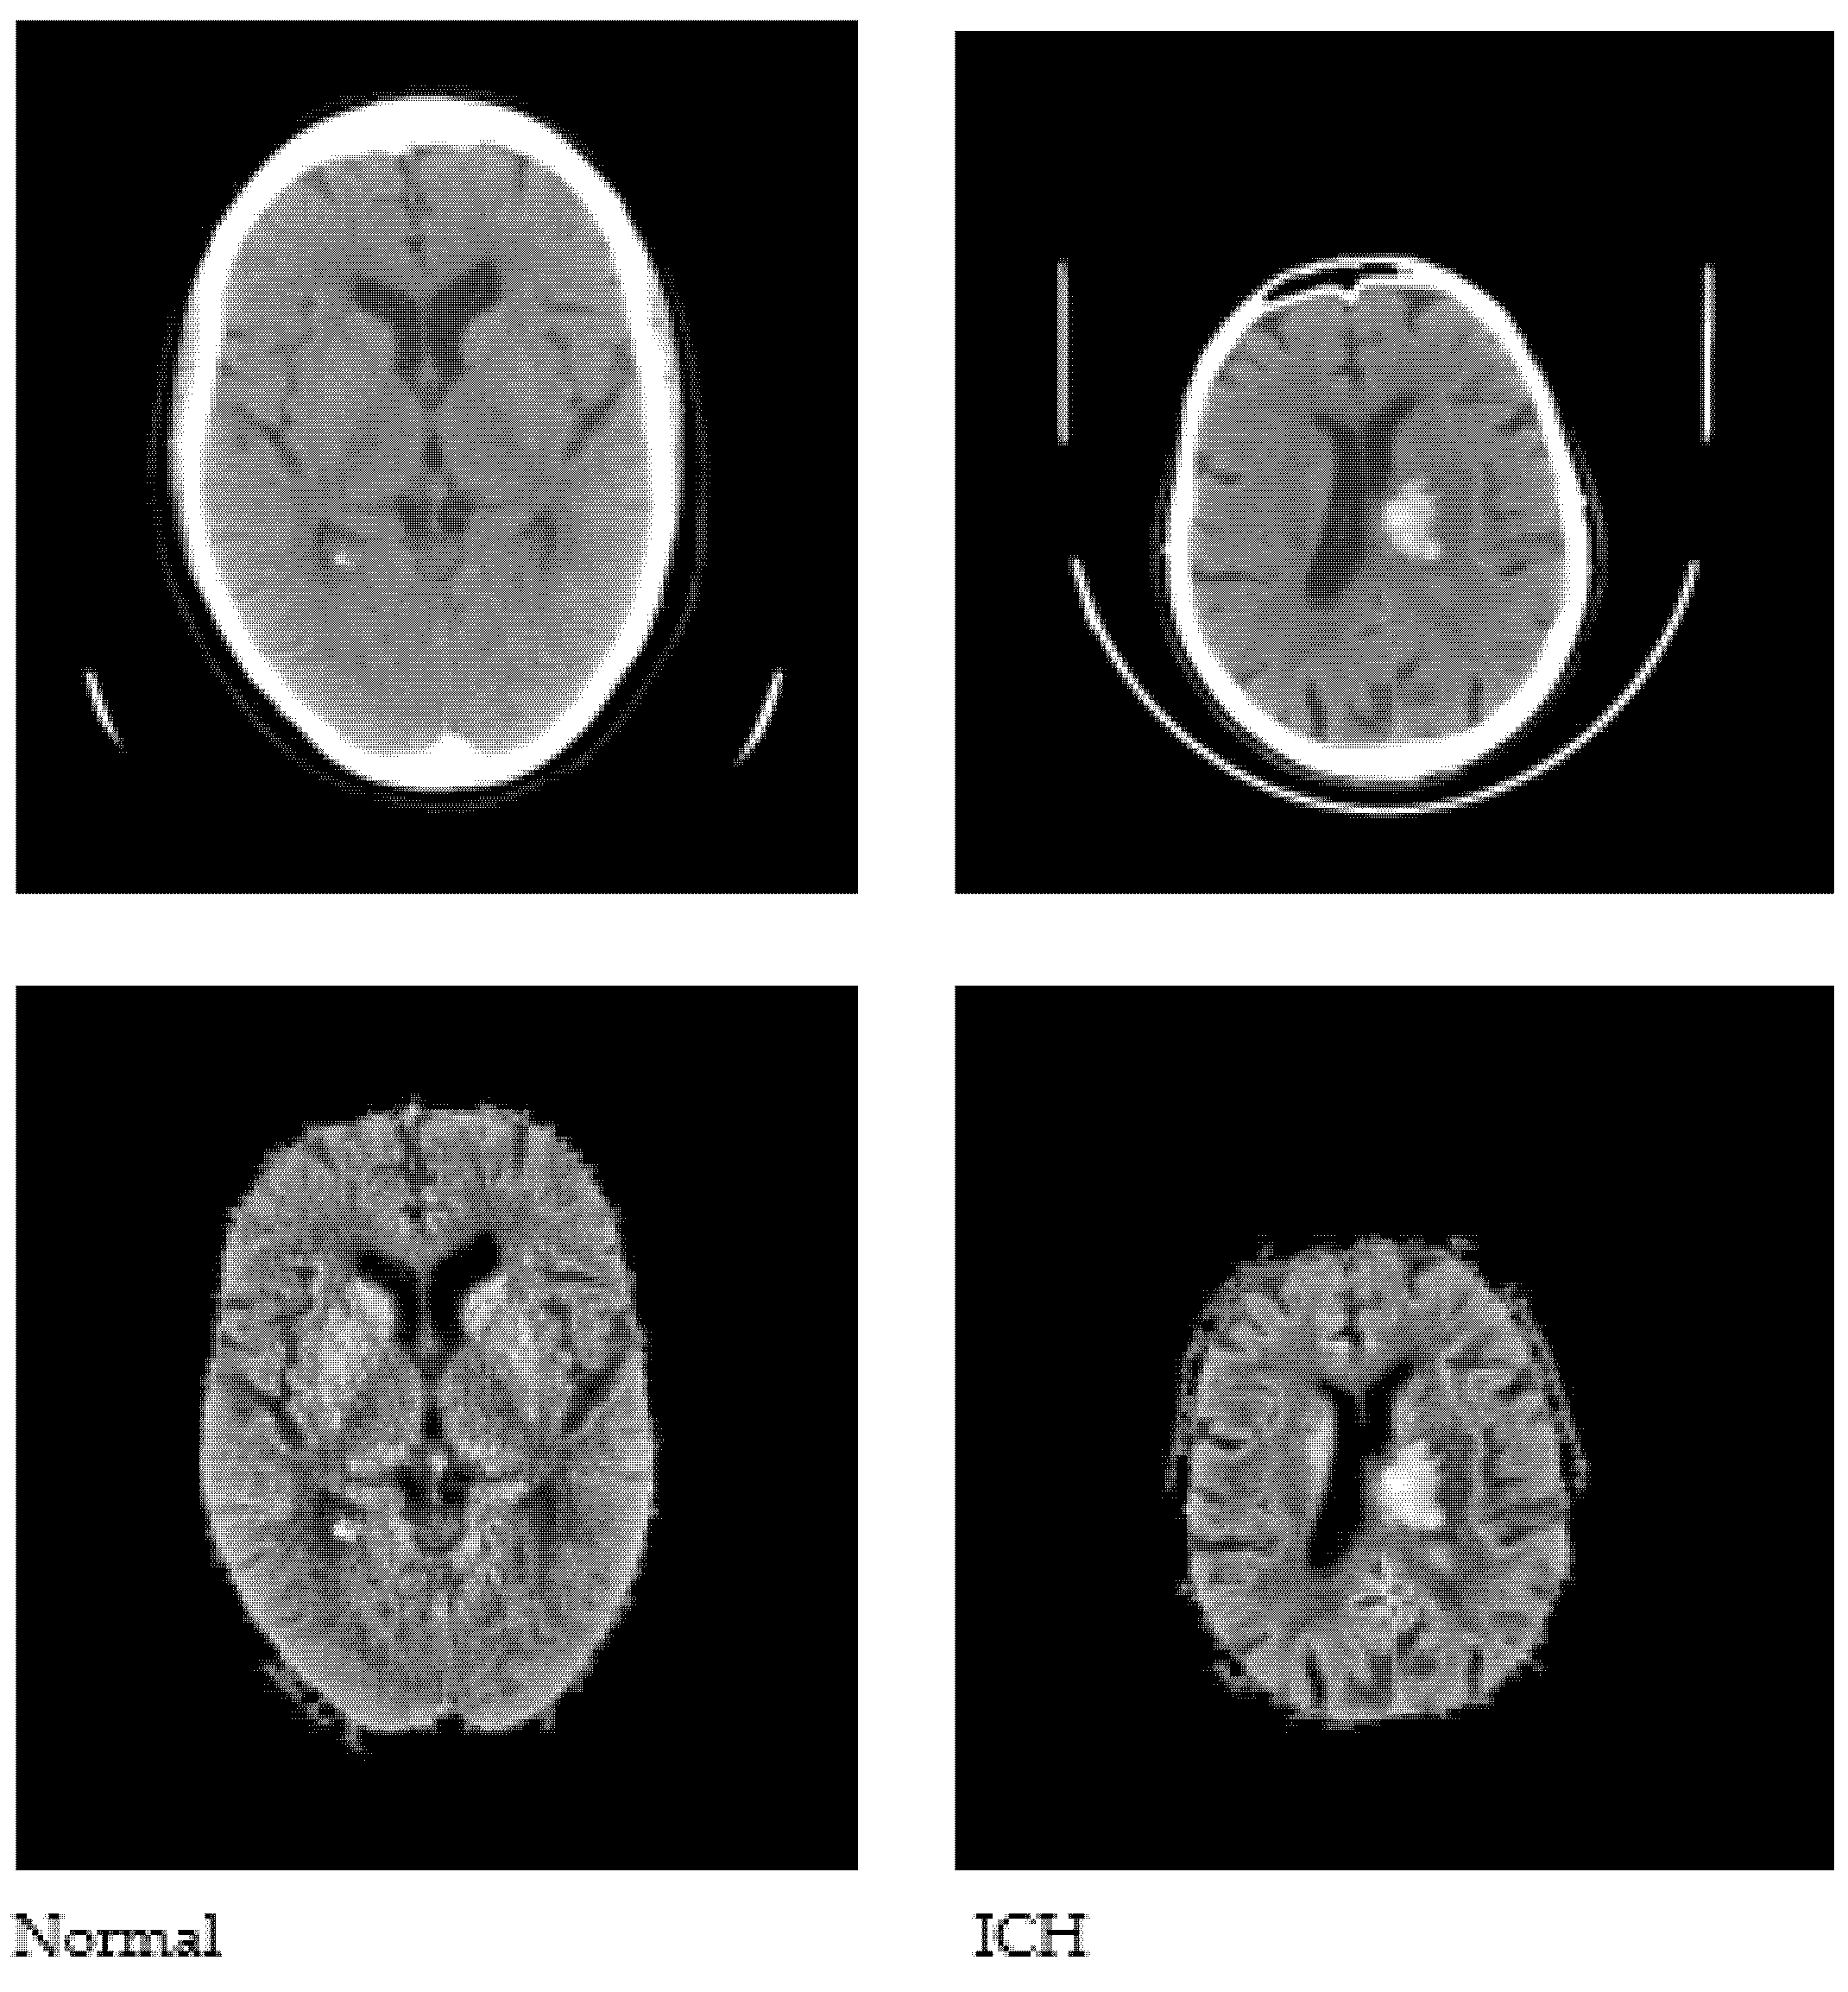

We used the publicly available CQ500 database to conduct this study. The CQ500 dataset [27] includes CT scans of 491 subjects that were employed to construct a Convolutional Neural Network (CNN)-based model for the classification of hematoma subtypes, calvarial fractures, and midline shift in a fully automated fashion. We used a total of 1831 CT images, of which 1000 are healthy and 831 are with hematoma. The CT images were initially converted to JPG format with a 512 × 512 dimension. A sample set of normal and abnormal axial CT images is shown in Figure 1.

Figure 1.

Sample CT images used to conduct the study.